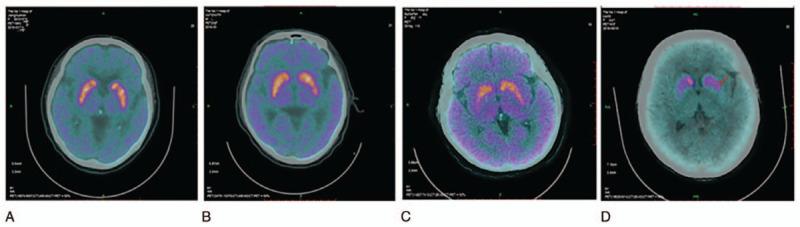

The value of dual imaging mode for the severity assessment of Parkinson disease (PD) is explored by conducting positron emission tomography computed tomography (PET/CT) double imaging using combined 18-fluorine flurodeoxyglucose (F-FDG) brain metabolism and 11C-2β-carbomethoxy-3β-(4-fluorophenyl) tropane (C-CFT) brain dopamine transporter (DAT).A total of 102 patients with PD and 50 healthy people in the control group are enrolled for the PET/CT dual imaging of F-FDG brain metabolism and C-CFT brain DAT. The characteristics of F-FDG PET/CT and C-CFT PET/CT imaging are analyzed by delineating the region of interest. Differences in the glucose metabolism and DAT distribution in the basal ganglia of patients with PD and healthy control group in the PET/CT imaging and the radioactive distribution characteristics of cerebral cortex in glucose metabolism imaging are compared. The characteristics of PET/CT imaging of C-CFT brain DAT in the ganglion region in absorbing C-CFT in different PD groups are analyzed.Compared with the healthy control group, changes in the cerebral glucose metabolism in the PD group mainly occur due to the increased symmetry metabolism of the nucleus of bilateral basal ganglia and the decreased metabolism of the cerebral cortex as shown in the F-FDG PET/CT images. With disease progression, the bilateral parietal, frontal, temporal, and occipital leaves showed different degrees of FDG metabolism. Statistically significant difference is observed for theC-CFT absorption among the caudate nucleus and the anterior, middle, and posterior nuclei of the bilateral basal ganglia of the PD and healthy control groups. In the PD group, the bilateral caudate nucleus and the anterior, middle, and posterior parts of the putamen show decreased DAT distribution. Regardless of unilateral or bilateral symptoms, the DAT distribution in the nucleus of the contralateral basal ganglia and in the posterior part of the nucleus is substantially reduced.PET/CT dual imaging by F-FDG PET/CT combined with C-CFT PET/CT features high application value for the severity assessment of PD.

通过联合使用18-氟脱氧葡萄糖(F-FDG)脑代谢和11C-2β-甲氧基-3β-(4-氟苯基)托烷(C-CFT)脑多巴胺转运体(DAT)进行正电子发射断层扫描计算机断层扫描(PET/CT)双成像,探讨双成像模式对帕金森病(PD)严重程度评估的价值。共纳入102例PD患者和50例健康对照者进行F-FDG脑代谢和C-CFT脑DAT的PET/CT双成像。通过勾勒感兴趣区域分析F-FDG PET/CT和C-CFT PET/CT成像特征。比较PD患者与健康对照组在PET/CT成像中基底节区葡萄糖代谢和DAT分布的差异以及葡萄糖代谢成像中大脑皮质的放射性分布特征。分析不同PD组神经节区域C-CFT脑DAT在摄取C-CFT时的PET/CT成像特征。与健康对照组相比,PD组脑葡萄糖代谢变化主要表现为F-FDG PET/CT图像显示双侧基底节核团对称性代谢增加和大脑皮质代谢降低。随着疾病进展,双侧顶叶、额叶、颞叶和枕叶显示出不同程度的FDG代谢。PD组与健康对照组在尾状核以及双侧基底节前、中、后核的C-CFT摄取上存在统计学显著差异。在PD组中,双侧尾状核以及壳核的前、中、后部分DAT分布减少。无论单侧或双侧症状,对侧基底节核团及核后部的DAT分布均显著减少。F-FDG PET/CT联合C-CFT PET/CT的PET/CT双成像对PD严重程度评估具有较高应用价值。